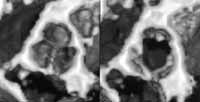

- В систему SONOS 5500 интегрирована уникальная цифровая технология получения трехмерных (3D) изображений сердца (Рисунок)с помощью омнипланового чреспищеводного или специального 3D мультипланового трансторакального датчиков. Новые датчики семейства Ultraband извлекают больше полезной информации, чем когда-либо ранее, благодаря использованию широчайшего диапазона частот. Кроме того, компания Хьюлетт-Паккард повысила верхнюю границу рабочего частотного диапазона датчиков Ultraband до 15,0 МГц. Одновременное сканирование на высоких и низких частотах позволяет добиться лучшей проникающей способности для визуализации глубоких анатомических зон или лучшего разрешения изображения или комбинации этих параметров для выявления текстуры ткани.

Увеличить

Рисунок. SONOS 5500, трансторакальный омниплановый датчик. Трёхмерная реконструкция аортального клапана в закрытом и открытом положении.